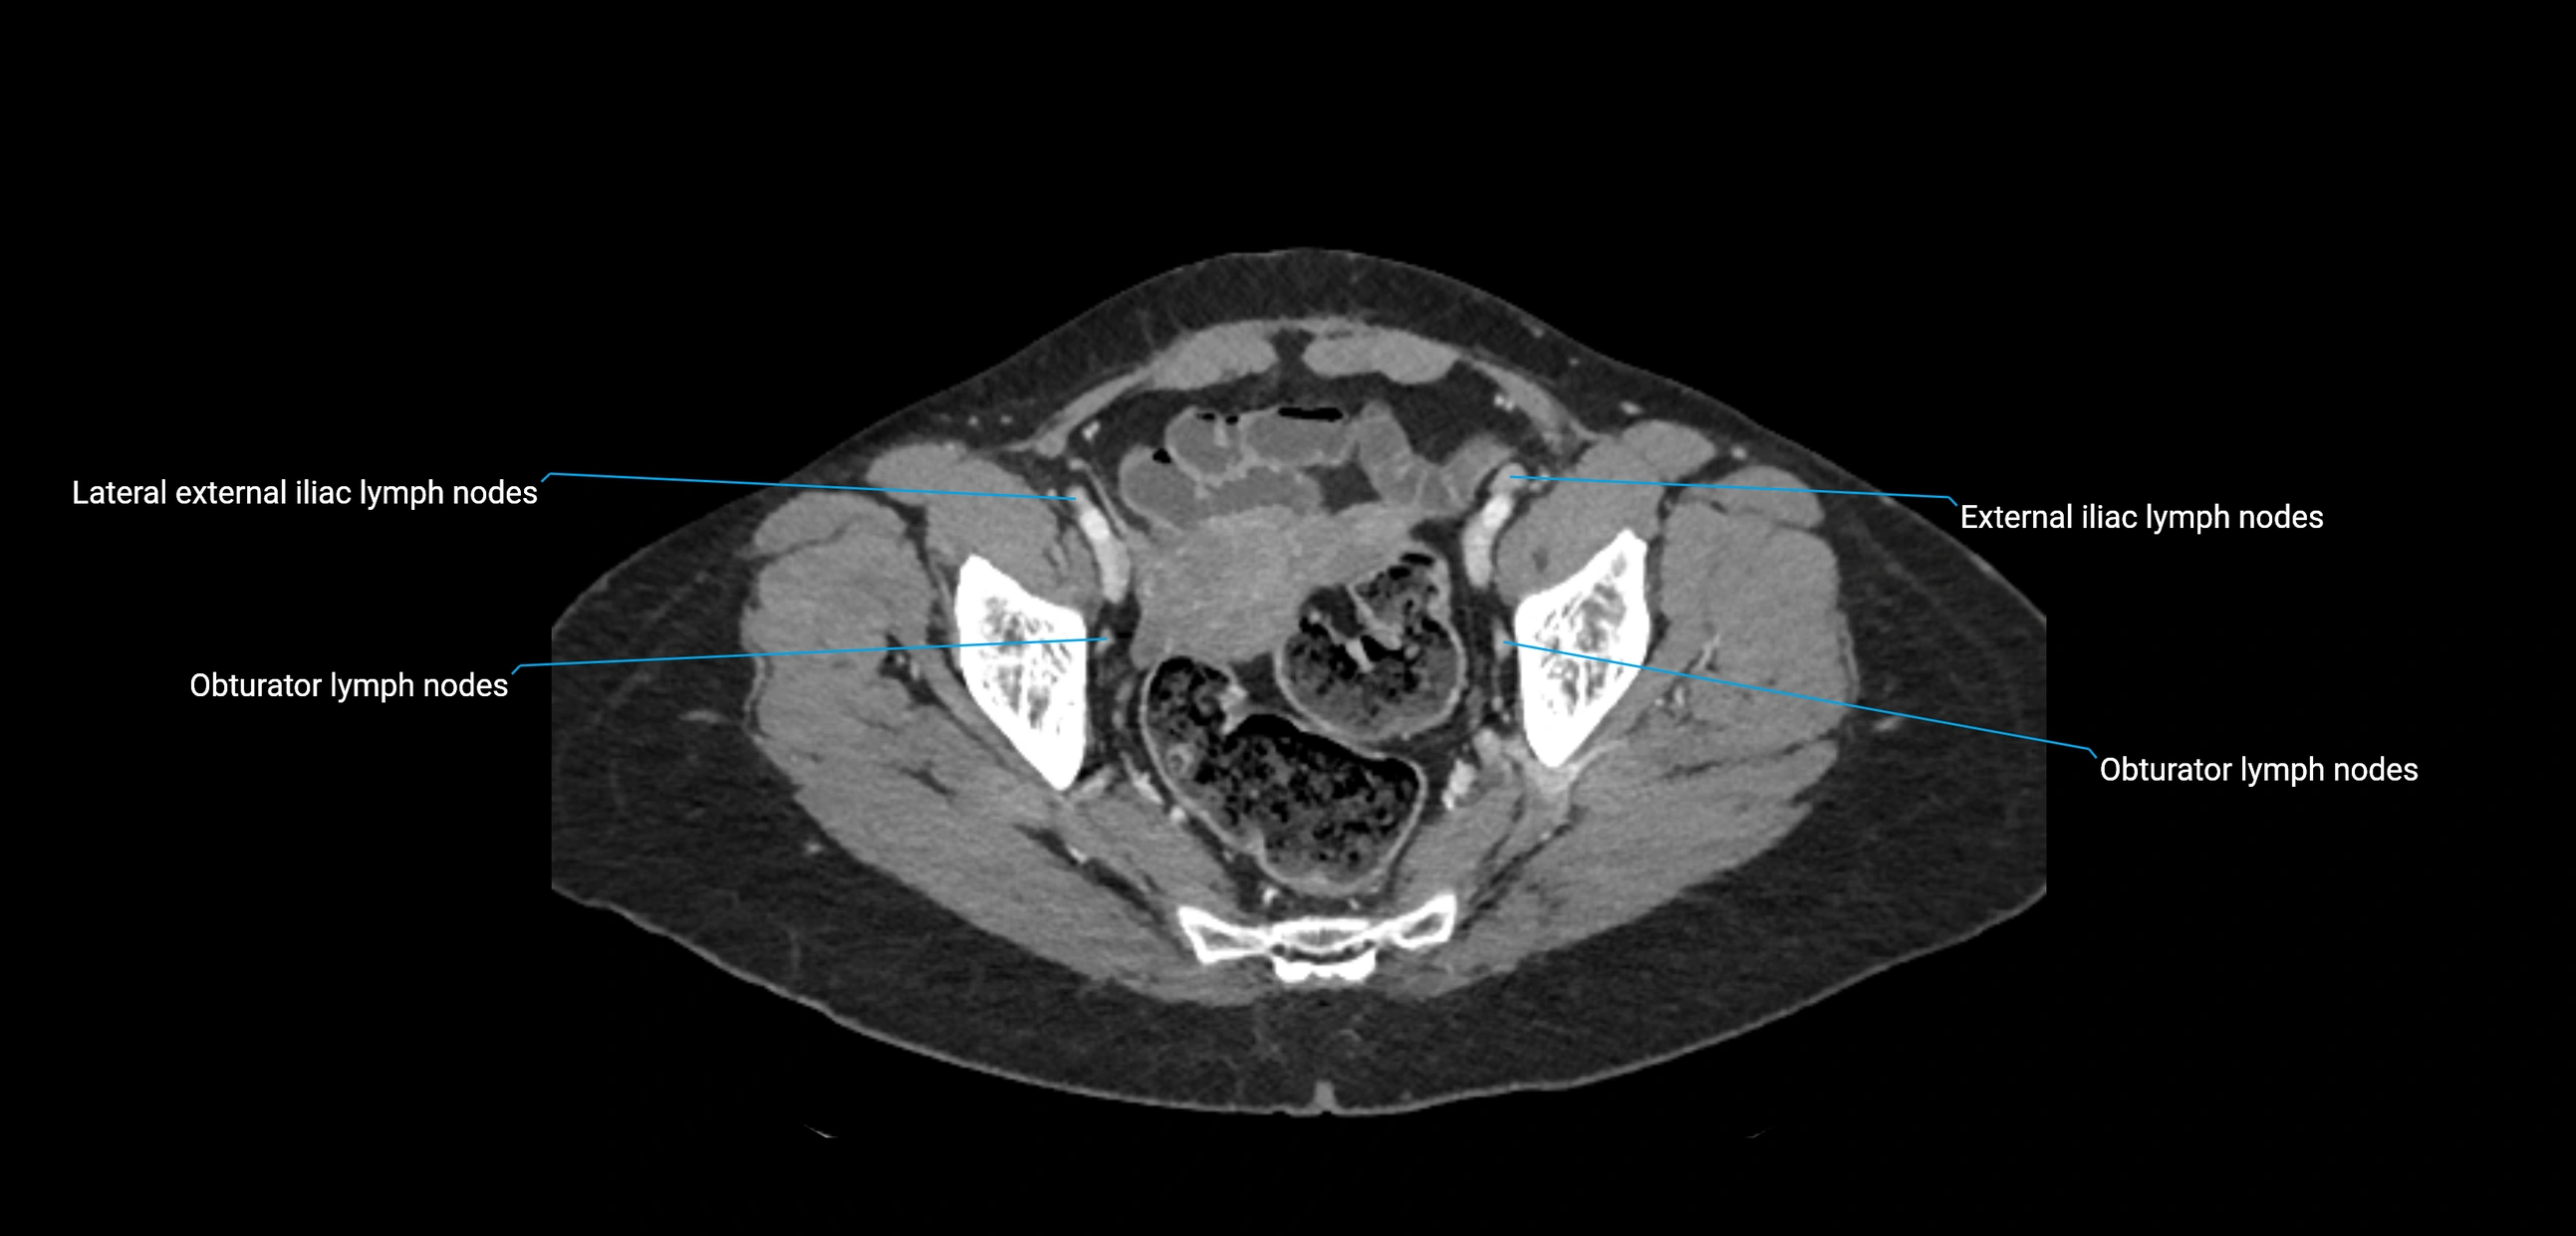

CT image

image